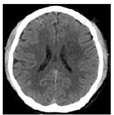

患者 男性,30岁,农民,既往体健,无感染及疫苗接种史。因"右侧肢体无力伴言语不清5个月余,加重8 d"于2018年5月23日入临沂市人民医院。患者于5个月前无明显诱因出现右侧肢体无力伴言语不清,持物不稳,右侧中枢性面瘫,在莒南县人民医院就诊,行头颅MRI平扫显示:左侧额叶、基底节区斑片状长T1长T2信号,弥散加权成像(DWI)显示高信号,诊断:脑梗死?住院期间,患者病情较前无改善,为求进一步诊治,经临沂市人民医院神经外科门诊,以"左侧丘脑恶性肿瘤"收入院。2017年12月21日患者行头颅CT扫描显示左侧基底节区、左侧侧脑室体旁斑片状低密度影(图1),并在全麻状态下行左顶穿刺基底节区病变活检术,征求家属同意后将病理切片送至北京神经外科研究所检验,病理诊断为"炎性脱髓鞘性假瘤",建议激素冲击治疗。当时患者病情较前好转,未同意。2017年12月23日行头颅MRI检查显示左侧额叶、基底节区、侧脑室体旁T2WI、T2液体衰减反转恢复序列(FLAIR)呈高信号;T1WI呈低信号;DWI显示高信号;注入钆喷酸葡胺对比剂后呈不均匀线性强化(图2)。